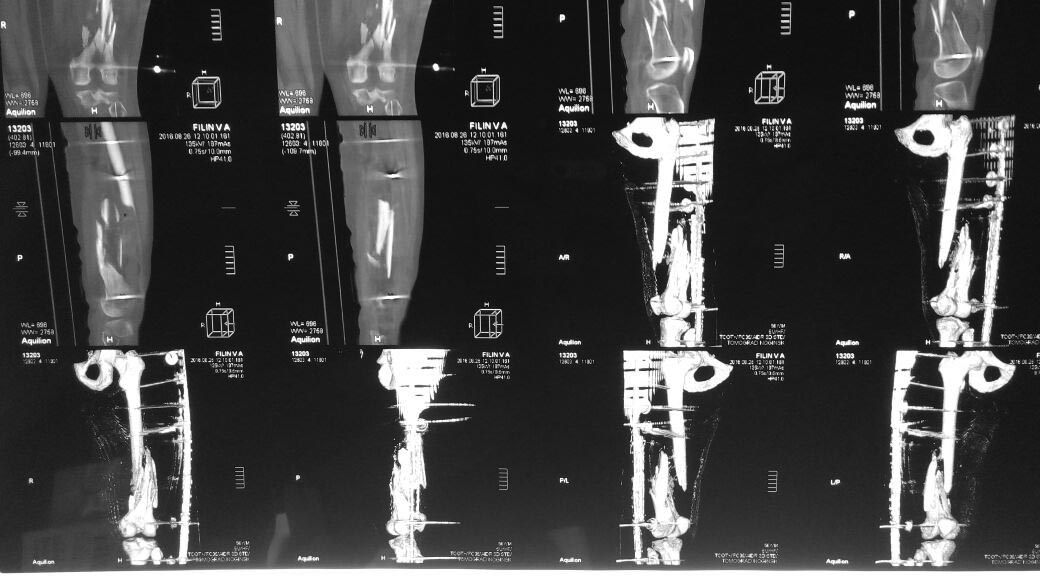

Уважаемые коллеги подскажите как бы вы поступили в данном случае

дальше?Травма 2 августа. О/перелом бедра. Рана была на передней пов.

бедра 5 см., протекала с серозным отделяемым (дренажи, вторичная х.о.,

а/б...).

Швы сняты 26.08.Кожа без воспаления. Температура в пределах 36 утром

37.1 вечером.В области мыщелков бедра стержень дает серозное отделяемое.

Мужчина трудоспособного возраста. Примерно под 100кг..